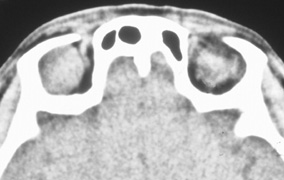

Fig. 6. Lateral orbitotomy through upper eyelid skin crease A. Photo demonstrating right globe ptosis present for more than 2 years. B. Axial CT scan showing a well outlined oval lesion in the lacrimal gland

fossa. C. Coronal CT showing lesion pushing globe inferiorly. D. Skin crease excision marked for lateral orbitotomy. E. Lateral orbital rim exposed. Bone cuts made above frontozygomatic suture